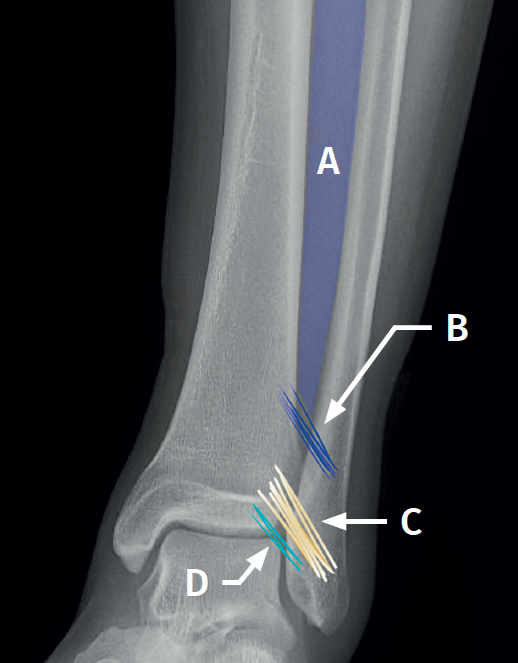

Arthroscopic evaluation of the syndesmosis

From the anteromedial portal we can directly visualize the distal fibers of the ATFL. Disinsertion of these fibers does not always result in instability of the syndesmosis, but it does require us to check it. In our experience, we prefer assessment of the coronal plane of the syndesmosis. We introduce the arthroscope into the tibiotalar joint directing the camera cranially. In this way we have a direct view of the distal tibiofibular joint. We then assess stability by attempting to insert the palpation probe into the joint. If it is possible to do so, we classify the syndesmosis injury as unstable (Figure 6A).

Arthroscopic evaluation of the deltoid ligament

There are multiple methods for assessing instability of the medial complex; using the anterior ankle portals it is possible to assess the stability of the deltoid ligament in its main plane of action, corresponding to the coronal plane. Chun et al.(20) described instability when it is possible to introduce an arthroscopic palpation probe into the medial tibiotalar space (Figure 6B). Vega et al.(21) reported that, in the majority of injuries, the most anterior portion of the deltoid ligament is detached from the medial malleolus, while its proximal insertions remain intact. In this situation, the arthroscopic palpation probe can be inserted between the medial wall of the internal malleolus and the deep fibers of the deltoid ligament.

It should be noted that injury to the syndesmosis causes disruption of the tibiofibular joint in the coronal and/or sagittal plane. The incidence of joint malreduction when compression clamp reduction is used is 16-52%(25,26). Given these percentages, the use of arthroscopy as a method for controlling reduction is growing in importance.

Surgical technique: arthroscopic treatment of acute syndesmosis injuries

The technique should be performed using the conventional anteromedial and anterolateral portals. The anteromedial portal is used for visualization, while the anterolateral portal serves as the working portal. Once the tibiofibular space is visualized, the inflamed synovial component is resected with an arthroscopic shaver to facilitate reduction (Figure 7A). Then, under direct vision, we restore the tibiofibular space, carefully taking into account possible malrotation of the fibula, especially in Maisonneuve type fractures. For fibular reduction we use a Verbrugge clamp, which allows us to correct the rotation. In our experience, once the space has been cleaned and if the position is correct, it is infrequent to have to use a compression clamp between the tibia and fibula.

Once the desired reduction has been achieved, we visually check the position and temporarily fix it using a Kirschner pin.

For definitive fixation, the surgical options range between rigid fixation with screws and dynamic fixation. Screws have been the standard procedure for decades, but involve complications, such as loosening or rupture. Furthermore, some surgeons advocate their removal, with the inherent risk of recurrence of instability(27). Dynamic fixation was designed to overcome some of these problems by allowing a degree of physiological movement of the syndesmosis, facilitating early weight bearing, reducing the risk of rupture, and eliminating the need to remove the implant (Figure 7B).